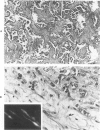

Pulmonary scar carcinomas and noncarcinomatous apical scars were subjected to collagen extraction, ultrastructural, and immunocytochemical studies designed to investigate the nature of their extracellular matrix. These studies revealed marked differences in both cellular and biochemical composition of scar carcinomas, compared with apical scars. Myofibroblasts, identified by antimyosin antibodies and confirmed by electron microscopy, constituted over 90% of the stromal cells of the scar carcinomas, compared with 0-10% in the apical scars. Collagen extraction studies revealed both an absolute and relative increase in Type V collagen in the scar carcinomas, compared with that found in the apical scars. The extracellular matrix of the pulmonary scar carcinomas was, however, identical to that of scirrhous carcinomas of the breast. These findings suggest that pulmonary scar carcinomas are probably desmoplastic carcinomas, rather than scar-arising tumors.